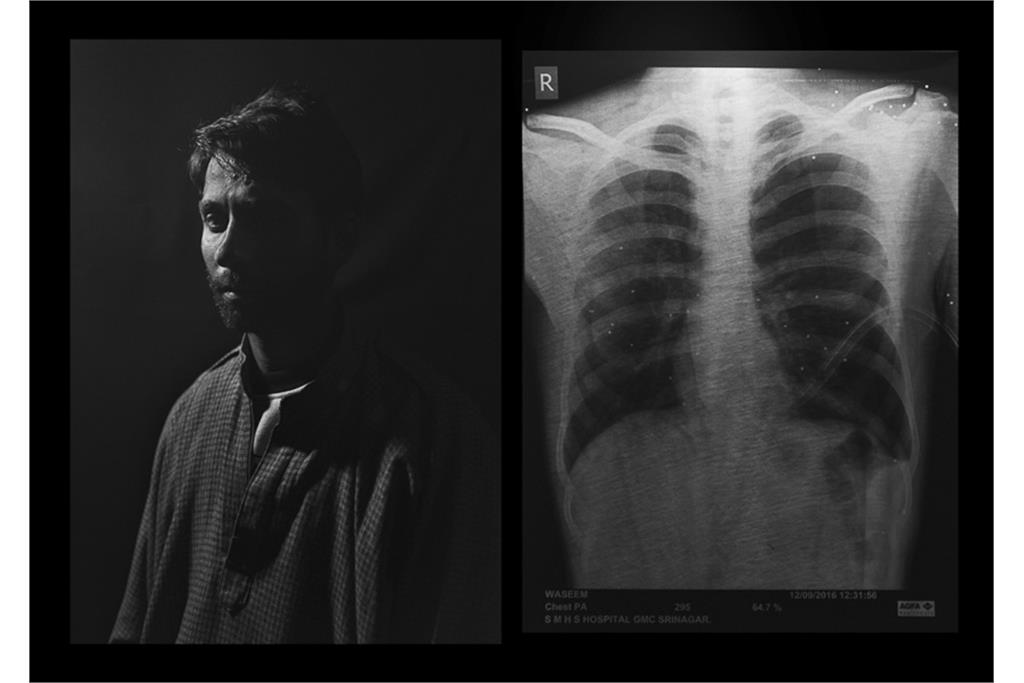

«دره‌ سایه‌ها» مجموعه‌ای از عکس‌ها و اسناد پزشکی در زمینه نقض سیستماتیک حقوق مردمان کشمیر و اعمال شدید‌ترین خشونت‌های دولتی در سرکوب آنها است و نشان دهنده سایه‌ سیاهی که بر دره‌ کشمیر افتاده است و مردمانی که از درون شکسته‌اند. هم‌نشینی بیرون(عکس‌های عادی) و درون (عکس‌های اشعه ایکس)‌ از افراد، تلنگر این فاجعه بر بیننده را دوچندان می‌کند.گویی درد پنهان و آشکار آن‌ها در تاریکی فرو می‌رود و از آن‌ها جز سایه‌ درد و نقطه‌های روشن ترکش‌های داخل بدنشان در عکس‌های اشعه ایکس چیزی باقی نمی‌ماند.